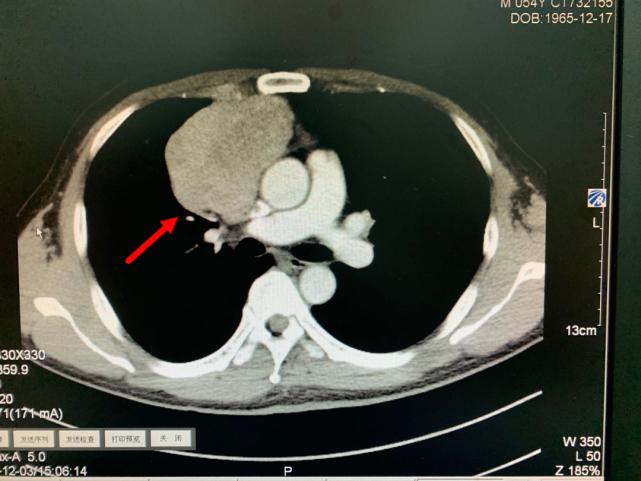

箭头所指为巨大纵隔肿瘤

肿瘤与周围血管存在黏连

今年11月份,老方因“肠炎”在浙江省立同德医院肛肠科住院。“新冠”期间住院需要常规做胸部CT筛查,检查出来的结果却让他和医生们大吃一惊,胸部CT显示:胸腔内存在一个巨大肿瘤即纵膈肿瘤,大小约10.0cm×6.5cm×7.0cm,大小和一个成人男性拳头差不多。肿瘤紧靠着肺部、心脏及大血管,且与部分大血管有粘连,对重要的脏器已经造成了挤压。在确定胃肠道没有严重病患后,老方被转入心胸外科进一步作检查、治疗。

叶中瑞主任医师通过进一步增强CT检查发现,老方体内的肿瘤巨大、与相邻的重要脏器粘连,界限不清,手术难度较大,且微创手术不适合,于是采取正中劈开胸骨的手术方式。手术过程顺利,术后恢复良好。第二天即下床活动。术后病理结果显示:纵膈肿瘤性质为中度恶性的胸腺肿瘤,后续还需要做进一步的放射治疗,以防止复发。老方在庆辛之余,他告诉叶中瑞主任医师,自己从今年开始每年都按时做体检,争取做到疾病早发现、早治疗,避免错过疾病的最佳治疗时机。